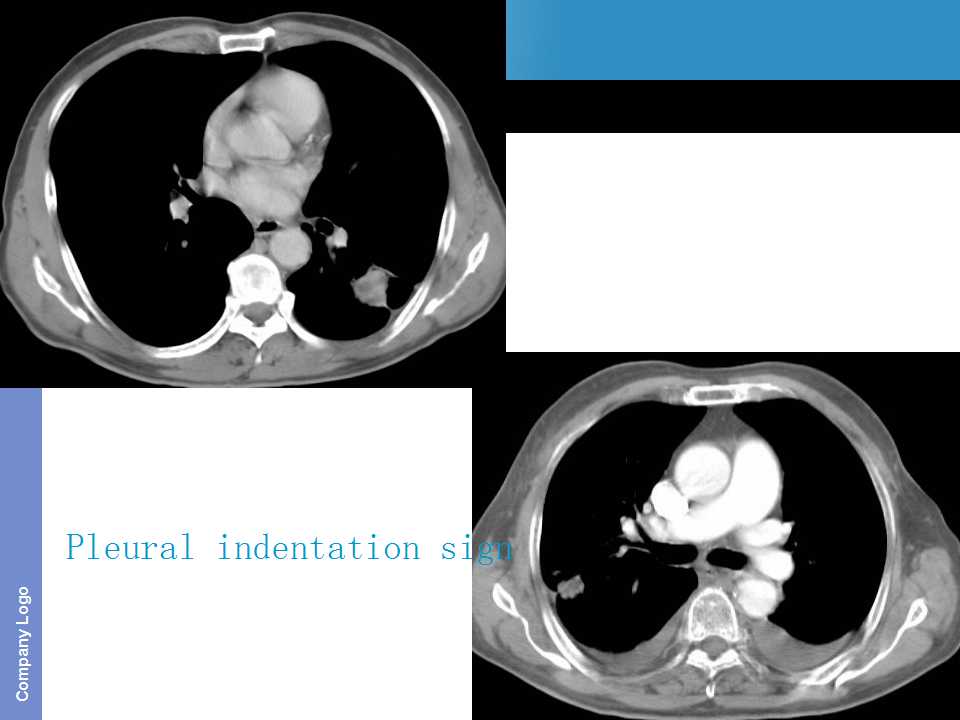

肺癌影像诊断